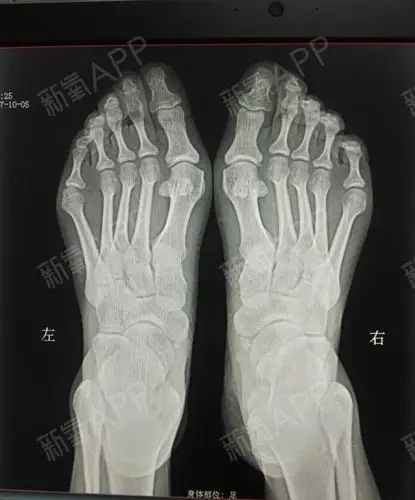

大脚拐,大脚趾内侧疼痛,要警惕:拇(趾)外翻,拇囊炎

我脚的问题有点多,不仅有大脚骨,还有脚趾畸形,小脚_圈子-新氧美容